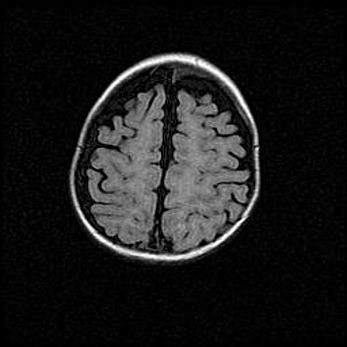

Церебральная ишемия II.

Возраст: 7 дней

Вес: 3350 г

Пол: женский

Окружность головы: 35 см

Срок гестации: 39 недель

Ишемия головного мозга – это состояние, которое развивается в ответ на кислородное голодание вследствие недостаточного мозгового кровообращения. У новорожденных она является следствием дефицита кислорода, что ведет к метаболическим расстройствам различной степени тяжести в тканях головного мозга, в том числе к развитию коагуляционных некрозов и гибели нейронов.